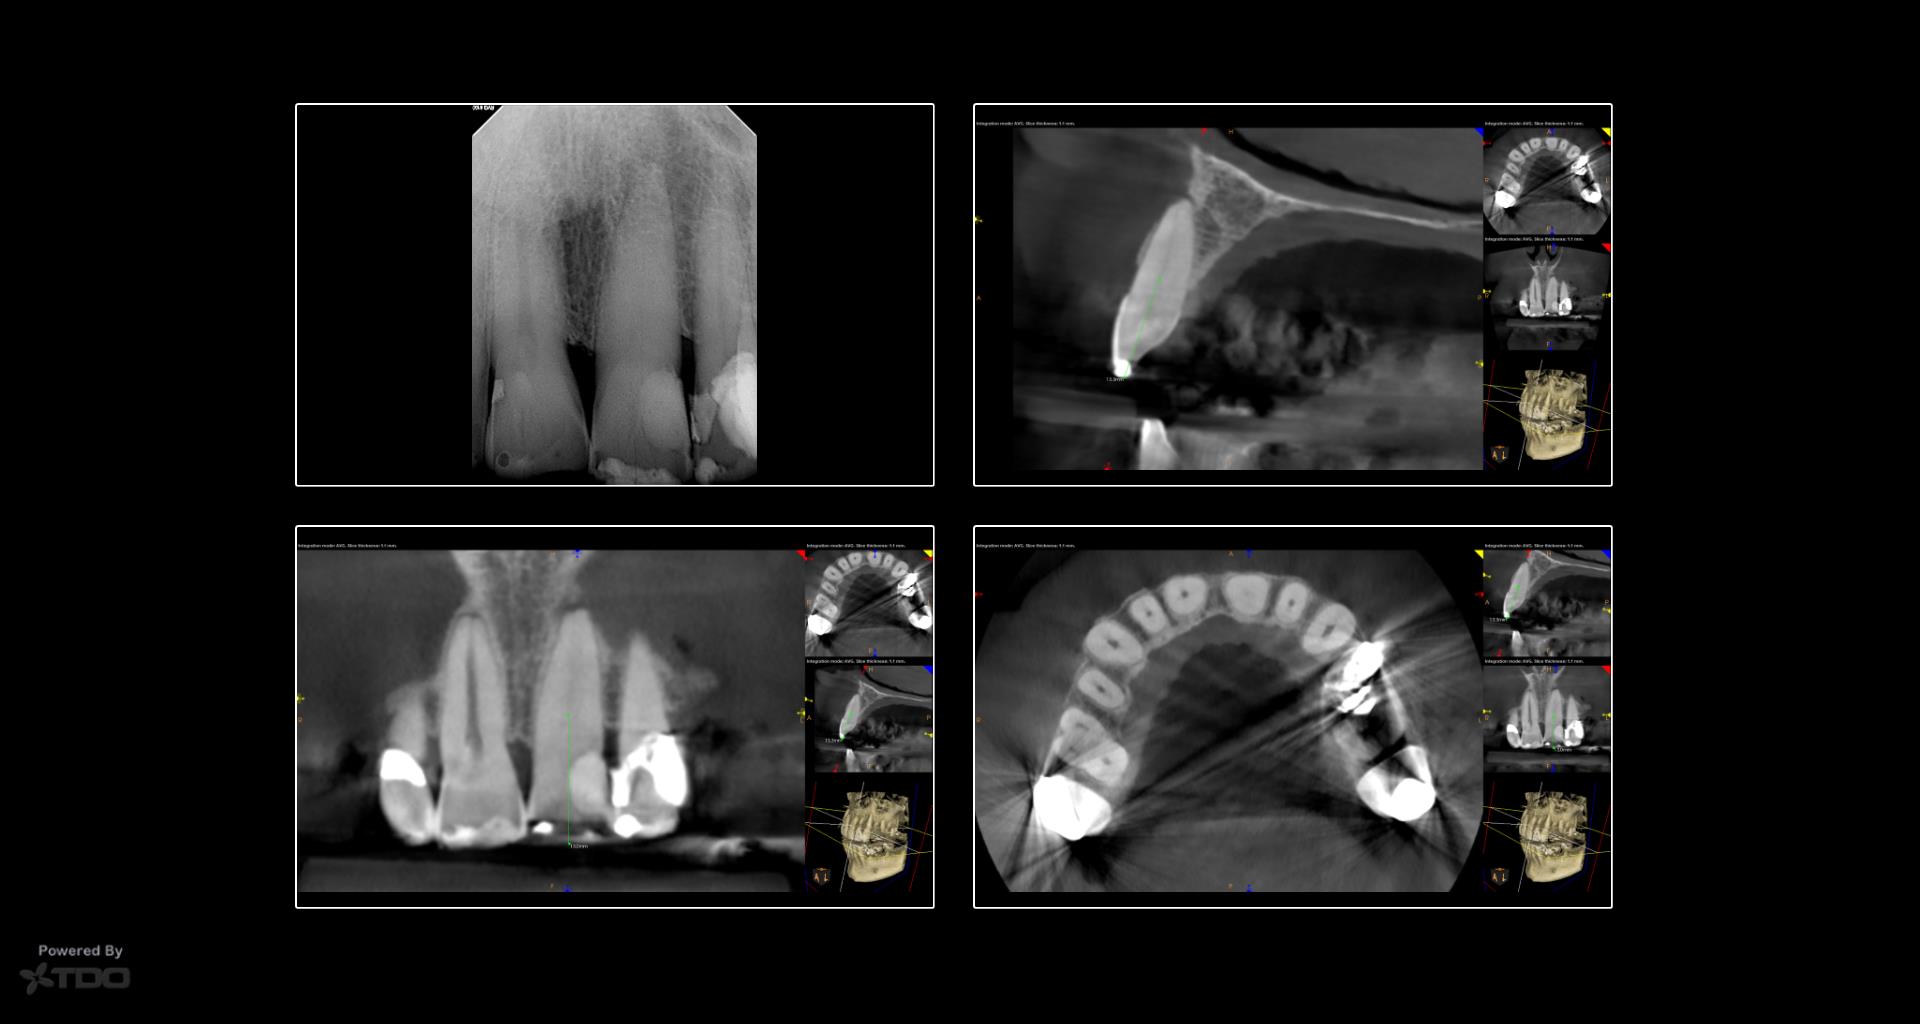

Dynamic navigation has been in dentistry for many years. It remains in its infancy in endodontics but is proving to be very helpful for the access of calcified teeth. This is a case from yesterday in which dynamic navigation was used to allow for a conservative access while locating the calcified canal. -Charles

For many cases I will utilize the exisiting restoration for the access. Due to the increased difficulty of the access of this case I made the choice to perform the access guided and with the angle to give me the best success to locate the canal conservatively. This goal was accomplished. Furthermore, going through the incisal edge does not go against the preservation of PCD. This is the area of concern.